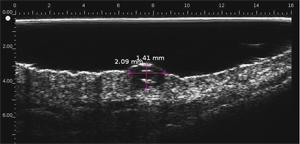

Melanomas Ecografía

Hipoecoica , con ecos de baja densidad. El eco de entrada no está muy marcado o ausente (ausencia de queratosis, ulceración) Melanoma ulcerado en el antebrazo (grosor medido a 3,68 mm en ecografía, grosor histológico). Lesión que infiltra la dermis. Melanoma en la oreja Carcinoma de células basalesCarcinoma de células basales en la frente (por encima de la arteria temporal)Carcinoma de células basales en la cara por encima del mastoidesCarcinomasuperficialCarcinoma pigmentado Nevo dérmico Lesión hipoecoica con muchos ecos, borde con la dermis adyacente mal definidoHistiocitofibroma  Lesión hipoecoica , pobremente limitada con muchos ecos.

• Melanoma superficial extenso, melanoma maligno; Índice de Breslow

• Determina el índice de Breslow para el melanoma maligno